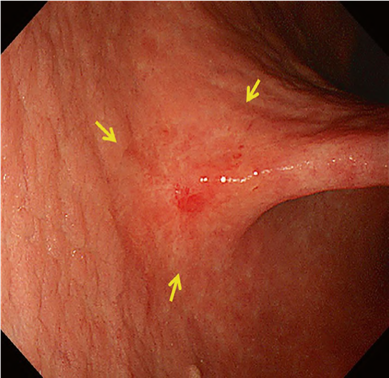

DL is defined as the border between the lesion and non-lesion areas, discernible through an abrupt change in MV and/or MS patterns (. Fig. 2).

The working group members carried out a systematic review of the English literature to determine widely accepted diagnostic systems. Consequently, the best-accepted diagnostic system was proven to be the VS classification system. Based on this system, MESDA-G was constructed using an evidence-based approach (. Figs. 3, 4, 5, and 6) [2]. First, lesions suspicious for EGC should be detected by careful inspection using conventional white-light endoscopy. Subsequently, magnified observations should be performed. Owing to the high sensitivity of the demarcation line [8], if it is absent, the suspicious lesion is diagnosed as noncancerous (. Fig. 4a, b). However, if the demarcation line is present, further assessment is required to determine the presence of an irregular MV or MS pattern. If an irregular MV and/or MS pattern is detected, the suspicious lesion is diagnosed as cancerous (. Fig. 6a, b) [1, 5, 6, 8]. If both the irregular MV and MS patterns are absent, the tumor is diagnosed as noncancerous (. Fig. 5a, b) [1, 5, 6, 8].